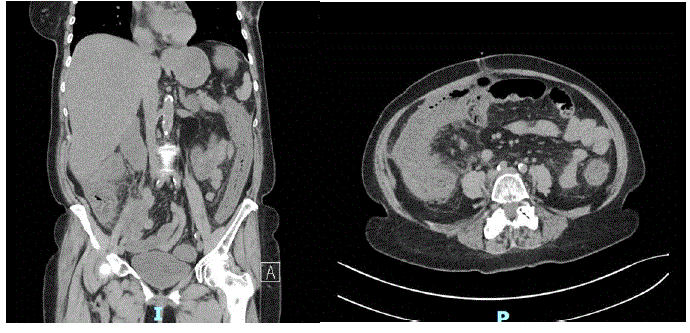

Realizada tomografia do abdome com os seguintes achados:

Qual é a melhor conduta no trauma abdominal?